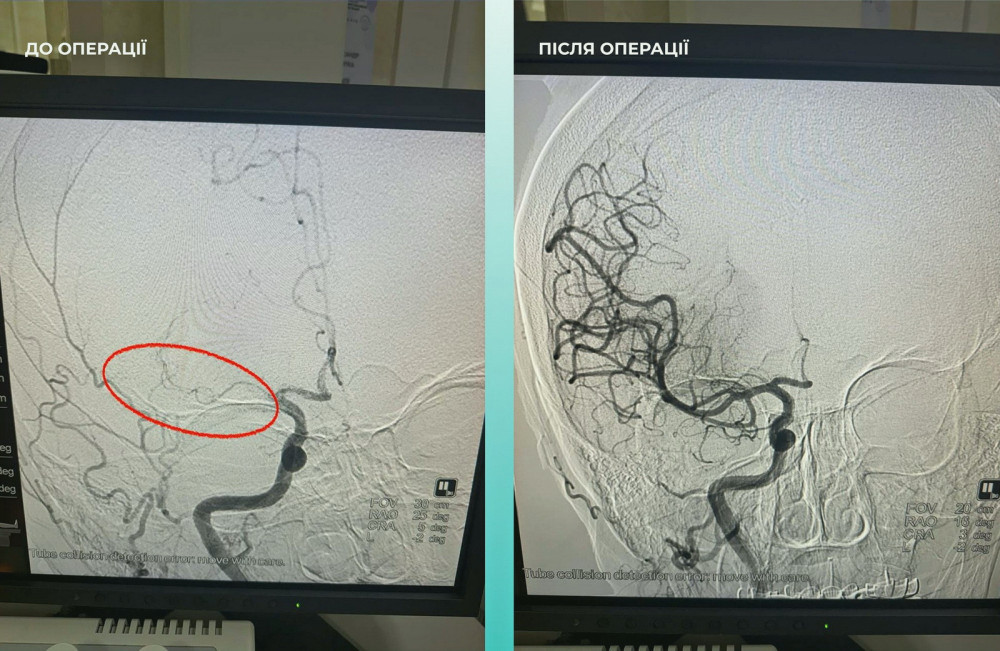

Пациентка поступила в больницу с тяжелым острым инсультом. При проведении компьютерной томографии врачи обнаружили закупорку средней мозговой артерии.

Мультидисциплинарная команда врачей приняла решение провести одновременную тромбоэктомию на мозговых и легочных артериях, что стало критически важным шагом к спасению жизни.

Операция прошла успешно. Пациентка чувствует себя намного лучше: она в сознании и уже начала двигать конечностями.